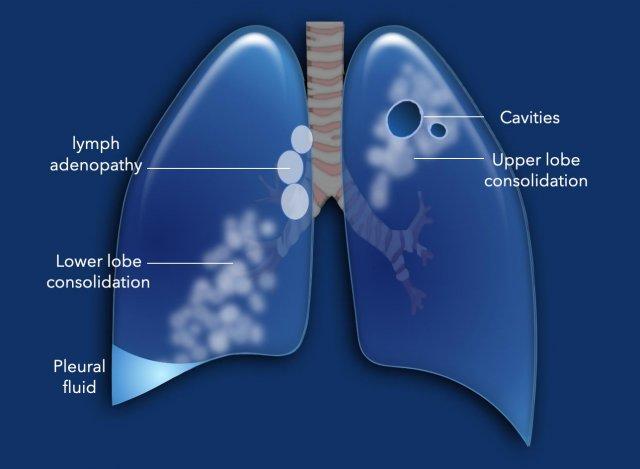

Hình minh họa này tóm tắt các dấu hiệu khác nhau trong lao hoạt động.

- Hạch to không kèm nốt phổi là dấu hiệu thường gặp ở trẻ em và có độ đặc hiệu cao cho lao.

- Đông đặc do lao không thể phân biệt với viêm phổi do vi khuẩn. Đông đặc mạn tính, hạch to và không đáp ứng với kháng sinh thông thường là các yếu tố ủng hộ chẩn đoán lao.

- Tràn dịch màng phổi là biểu hiện thường gặp của lao hoạt động và đặc biệt thấy ở trẻ em và bệnh nhân HIV có số lượng CD-4 thấp.

- Tạo hang có độ đặc hiệu cao cho lao.

- Lao kê là kết quả của sự lan tràn theo đường máu đến phổi và các cơ quan khác.

- Hình ảnh “cây nảy chồi” (tree-in-bud) điển hình cho sự lan tràn nội phế quản hoạt động của nhiễm trùng. Trước đây được cho là đặc hiệu cho lao, nhưng có thể gặp trong các nhiễm khuẩn khác.